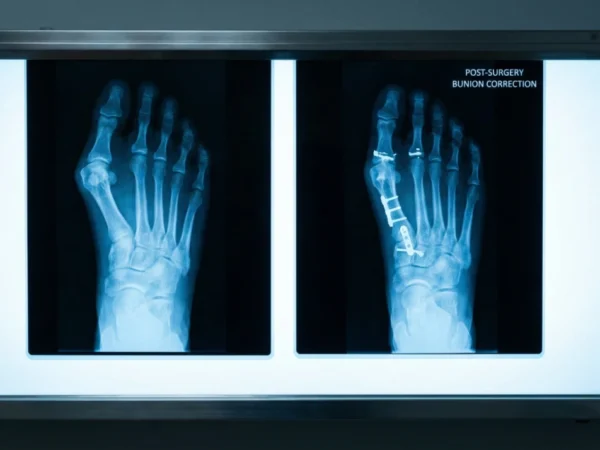

Modern Surgery on Bunions and Clinical Innovations

When pain limits daily activity and conservative measures fail, surgery on bunions is considered the most effective solution. In the US, more than $450,000$ corrections are performed annually.

Lapiplasty® 3D Bunion Correction: A breakthrough technology that addresses the rotation of the bone rather than just the angle. This reduces the recurrence rate to approximately $3\%$, compared to $30\%$ with traditional methods.

Minimally Invasive Surgery (MIS): Surgeons perform the correction through tiny $3$ mm punctures. This results in minimal scarring, reduced post-operative pain, and a faster return to daily life.

The bunion surgery recovery timeline has been significantly optimized. While traditional procedures often required weeks of total rest, modern 3D techniques allow many patients to begin protected weight-bearing in a specialized boot within $3$ to $10$ days. Full recovery and a return to regular footwear typically occur between 3 and 6Â months.